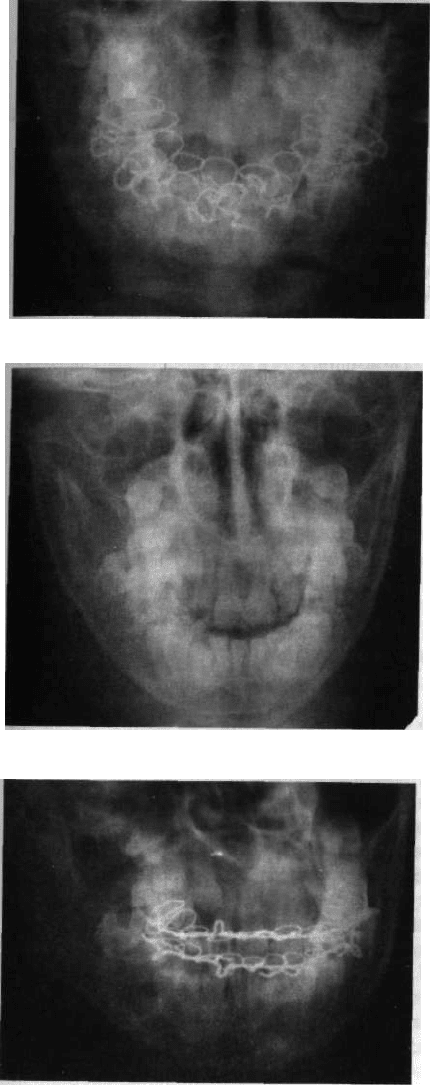

Для однобічних переломів виросткового відростка, які частіше виникають

у разі падіння на підборіддя, характерним є: 1) обмежене відкривання рота та

наявність болісного набряку привушної ділянки; 2) асиметрія обличчя за раху-

нок зміщення щелепи у бік перелому; 3) біль з боку перелому під час надавлю-

вання на підборіддя; 4) зміщення середньої лінії у хворий бік (мал. 266). Урахо-

вуючи наявність рани на підборідді, лікар пункту невідкладної допомоги пови-

нен ретельно обстежити дитину для виключення відбитого перелому вирост-

кового відростка.

Мал. 266. Прикусудитини з переломом пра-

вого виросткового відростка (стрілками по-

значено зміщення центральної лінії різців у бік травми діти не можуть проаналізувати

перелому) свої відчуття, точно охарактеризувати